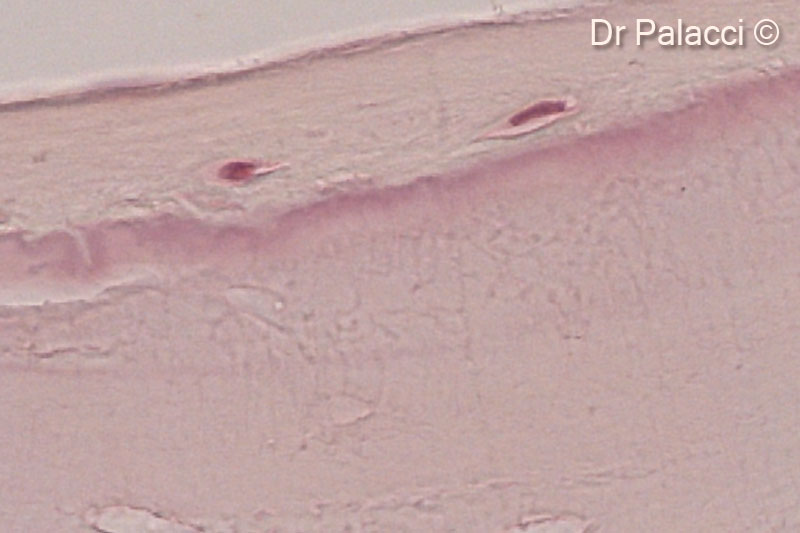

Một phần mẫu sinh thiết được lấy 4 tháng sau khi tăng cường bằng GTO. Các hạt vật liệu sinh học được bao quanh bởi xương mới hình thành, có sự hiện diện của các hốc tế bào xương